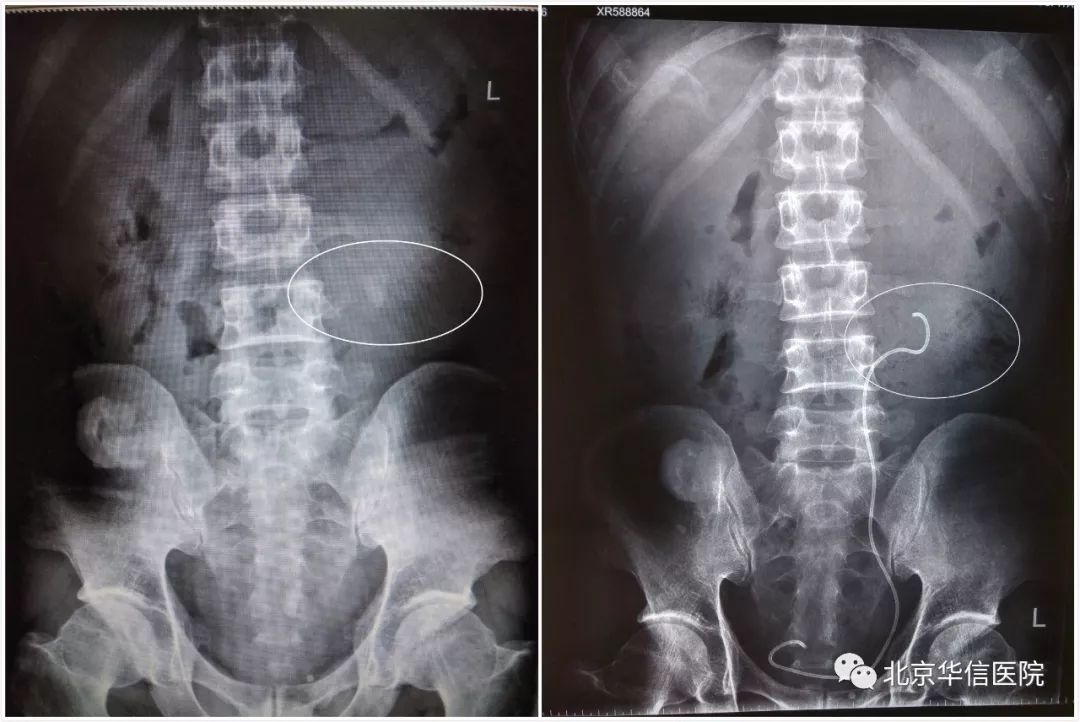

图左:手术前腹部KUB示左输尿管上段结石,图右:手术后腹部KUB示结石已清除